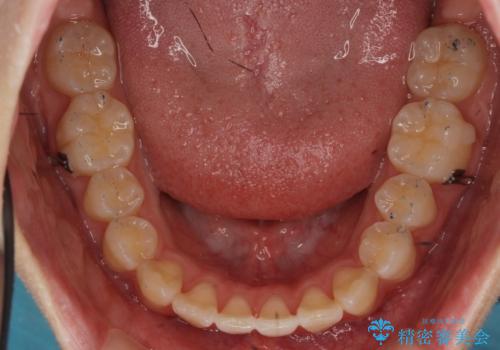

出っ歯 軽度のがたつき インビザラインで

- 20代女性

- インビザライン

- 奥歯を後ろに下げる処置をおこなっています。

前歯にオープンバイト気味の症状がありましたが、前歯を後ろに下げることでしっかりかませています。

前歯のずれも治り、しっかり下がりました。